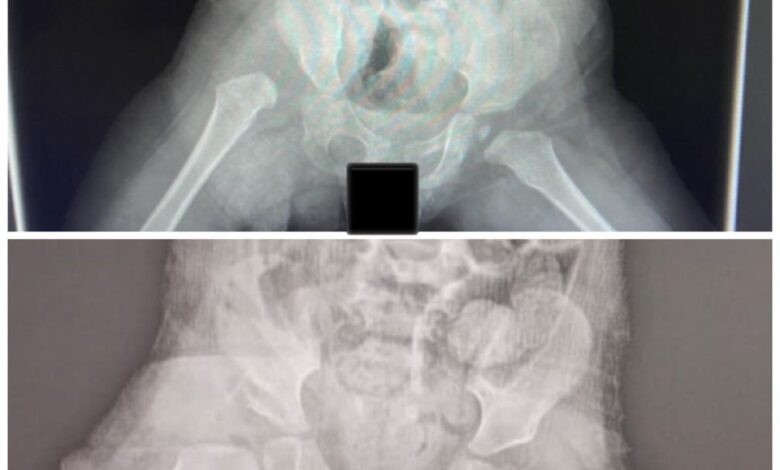

تمكّن – بفضل الله فريق طبي متخصص بجراحة عظام الأطفال بمستشفى الدرعية عضو تجمع الرياض الصحي الثالث ، في إعادة خلع الورك الولادي لطفلة بعمر 17 شهر .

وأضاف أنه تم من خلال فريق طبي يُشرف عليه استشاريي جراحة عظام الاطفال ، إجراء الفحوص والأشعات اللازمة وتهيئة متطلبات عملية التدخل الجراحي لإعادة خلع الورك لدى الطفلة، وتم بالشكل المطلوب، حيث استمرت العملية ساعتين تم خلالها إرجاع مفتوح لمفصل الورك. مع قص عظمة الحوض لتحسين التغطية وتثبيتهما مع تحرير الأنسجة حول المفصل، ووضعها في جبس بنطلوني لمدة ثلاثة أشهر.